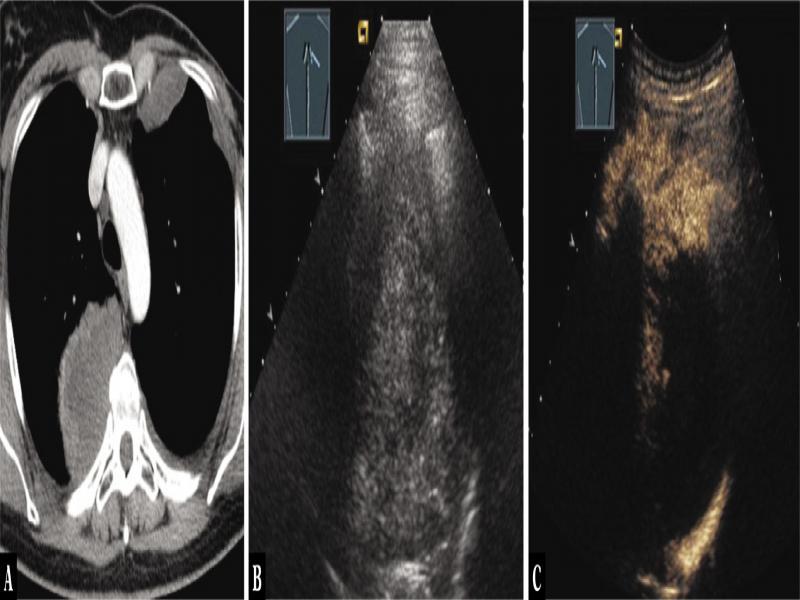

Fig. 1.

A 40-year-old female patient with mediastinal tumor in the anterior mediastinum as an incidental finding in computed tomography (A). Thoracic ultrasound indicated anechoic nodes (B), which showed no enhancement on contrast-enhanced ultrasound (C). Mediastinoscopy was performed, and regressive thymoma was histologically confirmed